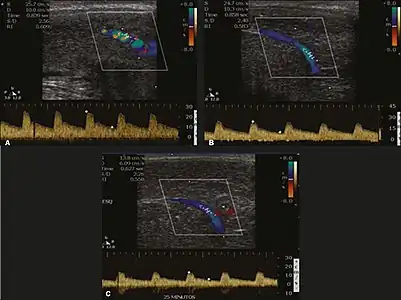

Erection can be induced by injecting 10–20 μg of prostaglandin E1, with evaluations of the arterial flow every five minutes for 25–30 min (see image). The use of prostaglandin E1 is contraindicated in patients with predisposition to priapism (e.g., those with sickle cell anemia), anatomical deformity of the penis, or penile implants. Phentolamine (2 mg) is often added. Visual and tactile stimulation produces better results. Some authors recommend the use of sildenafil by mouth to replace the injectable drugs in cases of contraindications, although the efficacy of such medication is controversial.[45]

Before the injection of the chosen drug, the flow pattern is monophasic, with low systolic velocities and an absence of diastolic flow. After injection, systolic and diastolic peak velocities should increase, decreasing progressively with vein occlusion and becoming negative when the penis becomes rigid (see image below). The reference values vary across studies, ranging from > 25 cm/s to > 35 cm/s. Values above 35 cm/s indicate the absence of arterial disease, values below 25 cm/s indicate arterial insufficiency, and values of 25–35 cm/s are indeterminate because they are less specific (see image below). The data obtained should be correlated with the degree of erection observed. If the peak systolic velocities are normal, the final diastolic velocities should be evaluated, those above 5 cm/s being associated with venogenic ED.[45]

Graphs representing the color Doppler spectrum of the flow pattern of the cavernous arteries during the erection phases. A: Single-phase flow with minimal or absent diastole when the penis is flaccid. B: Increased systolic flow and reverse diastole 25 min after injection of prostaglandin.[45]

Longitudinal, ventral ultrasound of the penis, with pulsed mode and color Doppler. Flow of the cavernous arteries at 5, 15, and 25 min after prostaglandin injection (A, B, and C, respectively). The cavernous artery flow remains below the expected levels (at least 25–35 cm/s), which indicates ED due to arterial insufficiency.[45]